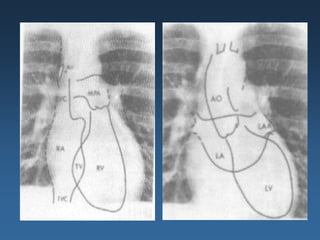

EXAMES – RADIOGRAFIA DE TÓRAX

INDICE CARDIOTORÁCICO

Linhas de Kerley: são finas

opacidades lineares

pulmonares causadas por

fluido ou infiltração do

interstício pulmonar.

Aumento da área cardíaca

Pulmões

Redistribuição do desenho vascular

Borramento hilar

infiltrado intersticial

Linhas B de Kerley

Edema alveolar

Derrame pleural